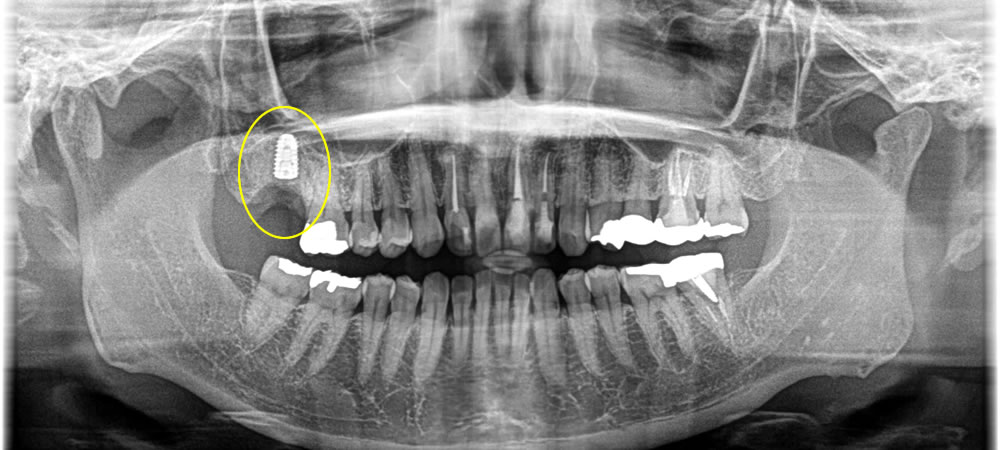

レントゲンでの検査の結果、根っこが大きく破折しているのが確認できました。歯を残すことは難しいことを伝えたところ、患者さまは抜歯とインプラント治療を希望されました。

抜歯即時埋入インプラントの実施

まずは、歯根が破折している当該歯を抜歯しました。

抜歯直後にインプラントを埋入しました。骨欠損の範囲が大きかったため、骨造成も同時に行いました。